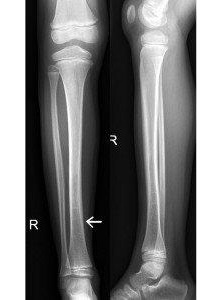

Undisplaced transverse fracture of tibia (arrow left)

Spiral fracture of tibia with minimal displacement